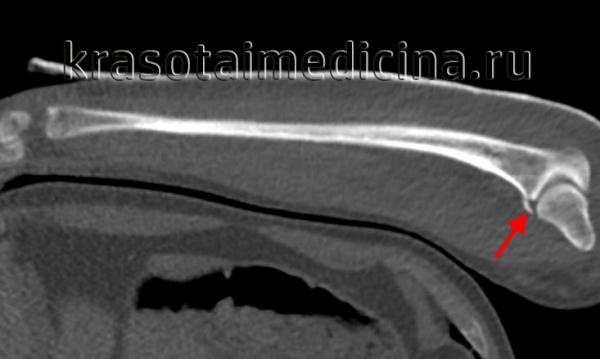

• Лучший диагностический критерий:

о Линейный перелом через локтевой отросток на боковой рентгенограмме локтевого сустава

(Слева) На боковой рентгенограмме локтевого сустава визуализируется небольшой отломок перелома кончика локтевого отростка. Края отломка неправильной формы, что отличает это повреждение от несросшегося центра оссификации апофиза.

(Справа) На боковой рентгенограмме у ребенка после падения определяется косой перелом через среднюю точку локтевого отростка с незначительным смещением. Напротив, зона роста локтевого отростка волнистая с выраженным кортикальным слоем по краям. (Слева) На боковой рентгенограмме локтевого сустава после падения на вытянутую руку при согнутом локтевом суставе виден смещенный отломок, оторвавшийся от кончика локтевого отростка. Степень смещения свидетельствует о значительном повреждении трехглавой мышцы.

2. Рентгенография при переломе локтевого отростка:

• Может быть разными от едва заметной линии перелома без смещения до сильного раздробления и смещения

• Обычно виден на боковой проекции

• Мелкий отломок со значительным смещением свидетельствует об отрыве трехглавой мышцы

Боковая проекция локтевого сустава позволяет увидеть перелом локтевого отростка с минимальным смещением без признаков перехода на венечный отросток. Лучеголовчатый и локтевой суставы сохранены. Здесь можно видеть боковую проекцию у этого же пациента. Проведена фиксация стягивающей проволокой. Стягивающую проволоку протянули в виде восьмерки и закрепили двумя спицами Киршнера. При простых переломах локтевого отростка это эффективное лечение, хотя осложнения, связанные с металлоконструкцией, наблюдаются часто. В боковой проекции локтевого сустава определяется сложный перелом дистального конца плечевой кости. Локтевой отросток интактен. Фиксация перелома плечевой кости потребует остеотомии локтевого отростка для доступа к плечевой кости. Здесь можно видеть боковую проекцию у этого же пациента после оперативной репозиции двухмыщелкового перелом плечевой кости. После остеотомии локтевого отростка наложена пластина и выполнена фиксация шурупами.